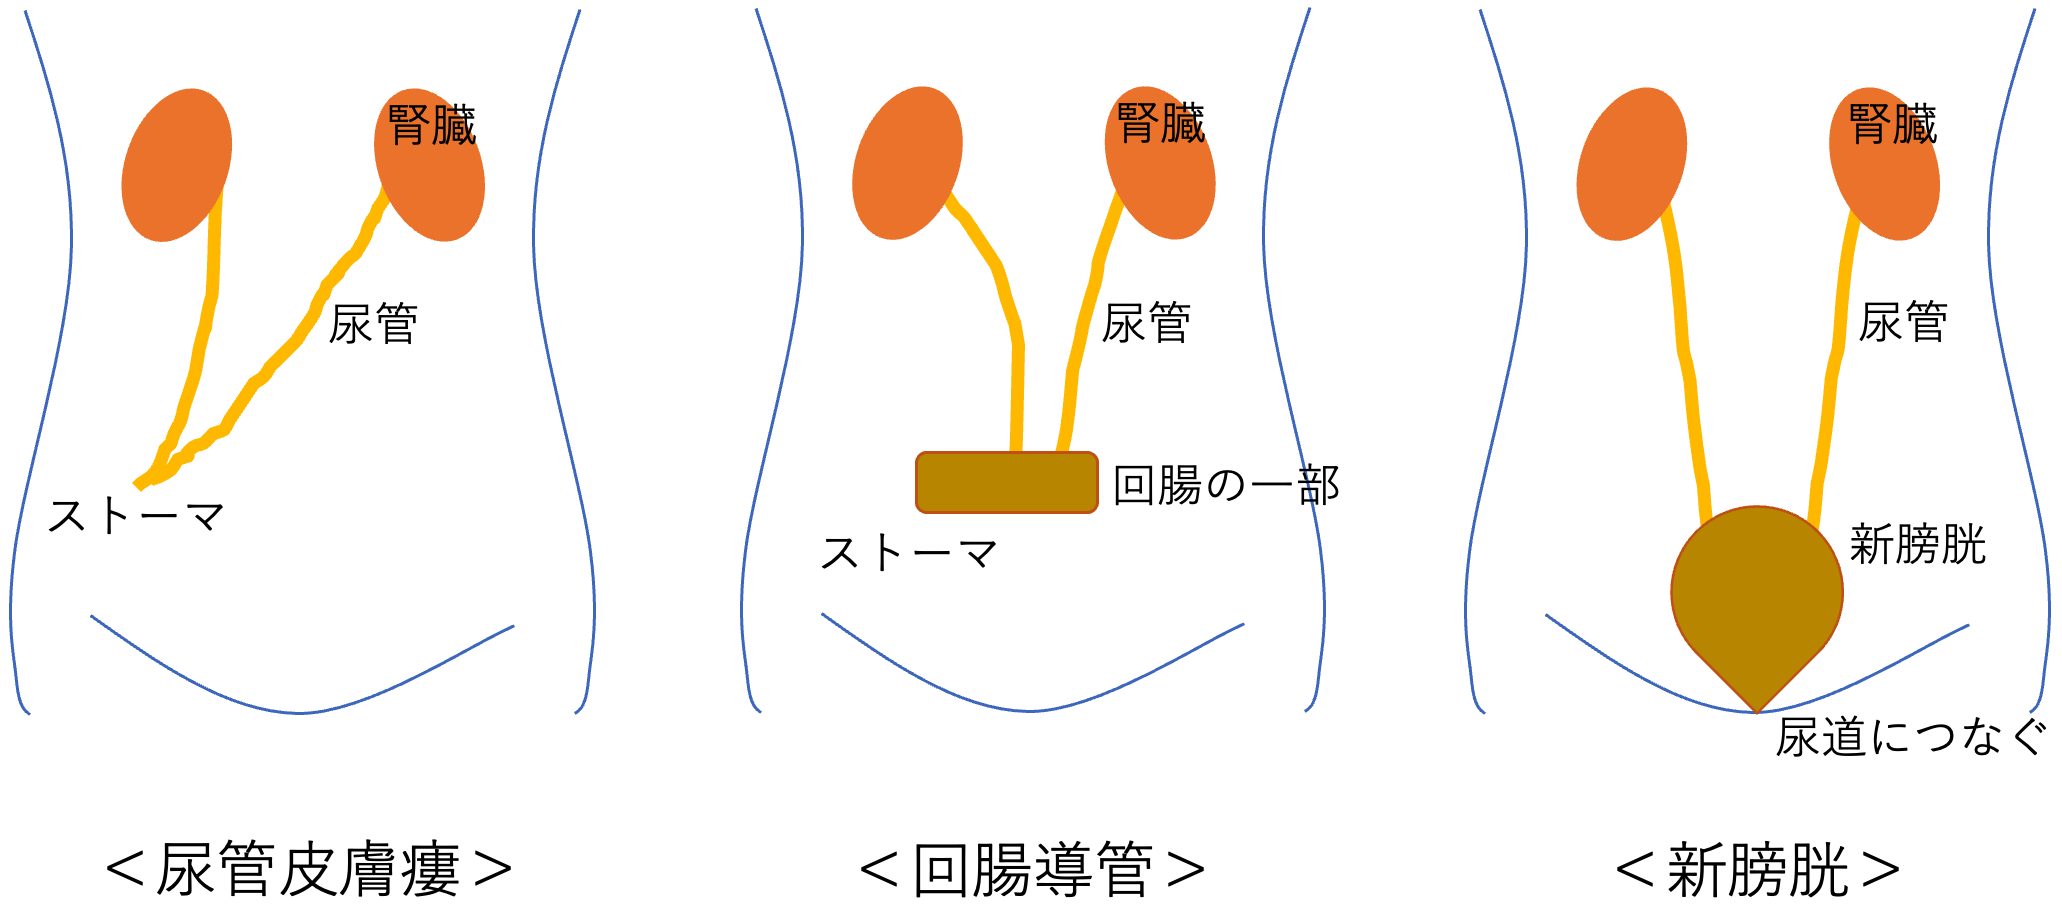

究める鏡視下膀胱全摘術・尿路変向術 Level up LRC, RARC | 三木。メジカルビュー社|泌尿器科|究める鏡視下膀胱全摘術・尿路変向。ロボット支援膀胱全摘除術(RARC) | 岩手医科大学 泌尿器科学講座。★3月精米★ 令和6年産 福井県産 いちほまれ 5kg 白米 精米。膀胱がん【泌尿器科疾患について】 - 東京慈恵会医科大学 泌尿器科。膀胱がん|KOMPAS。手術手技(膀胱全摘除術) | 領域情報 | アステラスメディカルネット。膀胱がん|KOMPAS。周術期の負担を軽減し早期社会復帰を!「ロボット支援腹腔鏡下。腎盂尿管移行部狭窄症に対するロボット支援腹腔鏡下腎盂形成術。朝倉書店『内科学』(第12版)デジタル付録。腹腔鏡下尿膜管摘出術及び左腎摘出術 - Olympus Professional。ロボット手術の定番!新品、未使用です。間違って2冊買ってしまったので、ページを開いてもいないため、本屋さんの「売上スリップ」も付いたままの全くの新品です。膀胱がんの外科治療について | 小野薬品 がん情報 一般向け。